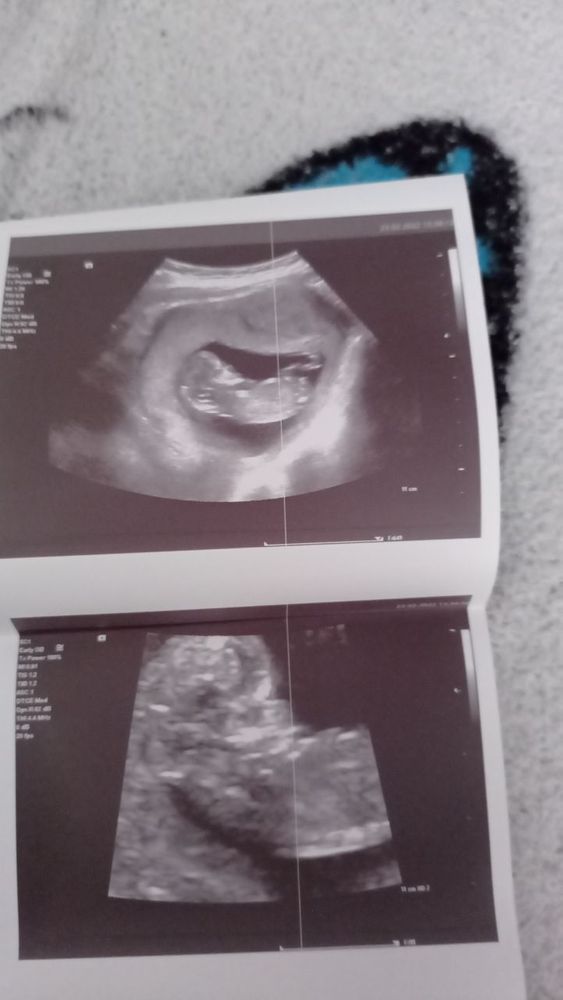

Пол ребёнка по узи, кто что видит?

Здравствуйте, видела тут девчонки на форуме, специалисты и видят по узи, нам уже 12 недель и 3 дня

Вижу девочку, но это не точно. Сейчас пока только предположить можно.